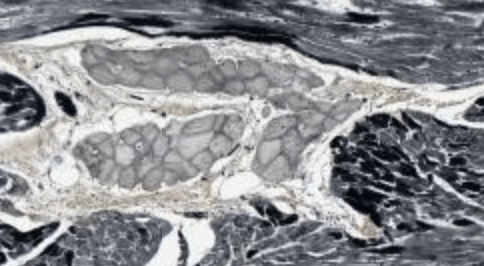

A type of small vessel disease caused by severe hypertension that causes onion-skinning of the vessel wall as shown.

What is hyperplastic arteriosclerosis?